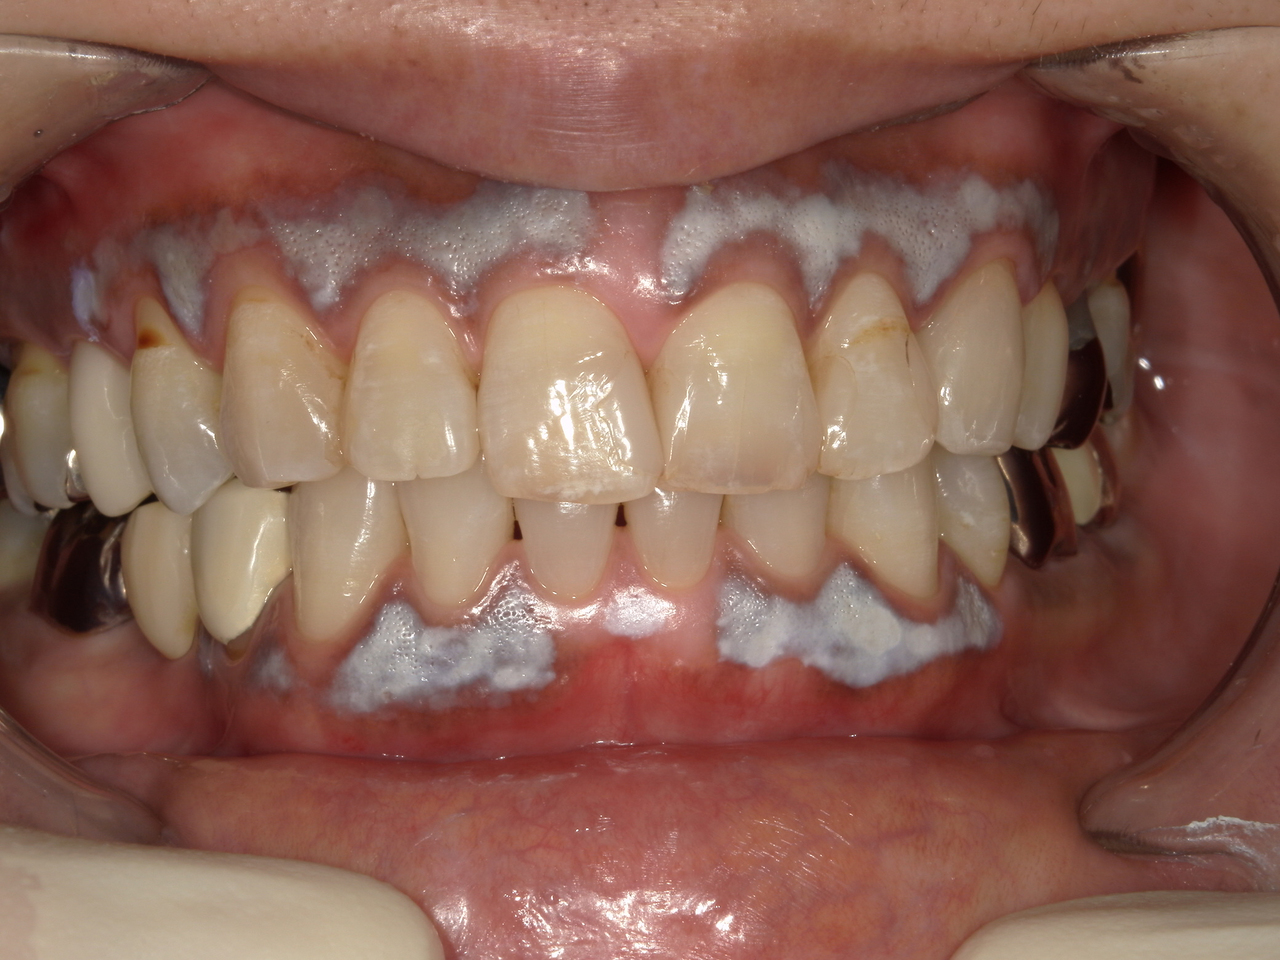

歯肉に喫煙によるメラニン沈着が

認められます。

ホワイトニング剤の塗布を行うと

白く変色します。